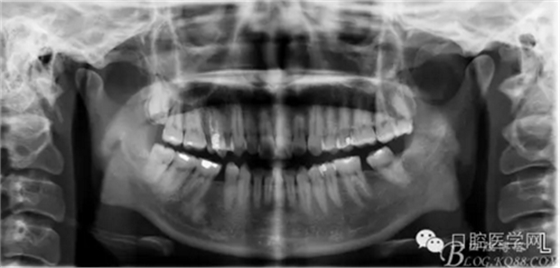

正畸醫(yī)生都想把患者做到“理想頜”,而臨床工作中卻很難如愿;這個(gè)患者到診時(shí),口內(nèi)已經(jīng)有兩顆恒牙缺失;

37,45缺失后,鄰牙近中移動(dòng)占據(jù)了部分牙位;患者要求減少治療費(fèi)用,不做種植修復(fù),那怎么協(xié)調(diào)右側(cè)的咬合關(guān)系?